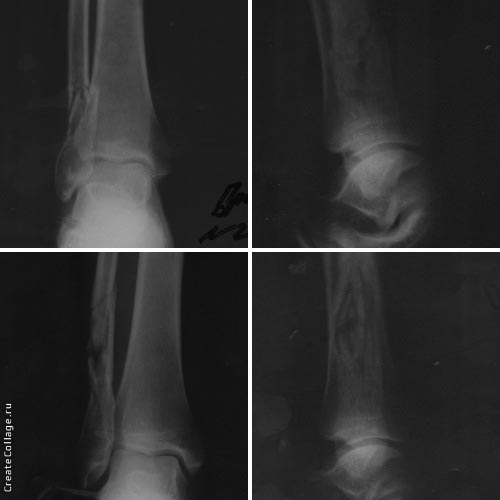

Пациент 36 лет, травму получил 14.03.2017 арматурой за то, что находился в неположенном месте в неположенное время.

По латеральной поверхности г/ст суставов - ушибленые раны по 3 см. При поступлении выполнена ПХО ран, наложены гипсовые повязки.

На данный момент раны зажили, отёчность уменьшилась.

Собственно вопрос, стоит ли оперировать лодыжки?

Какой бы ни был пациент, по представленным рентгенограммам - нет никаких показаний к оперативному лечению.

Травма прямая. С учетом локализации и механизма травмы нестабильности в г\стопном суставе быть не должно - консервативное лечение !